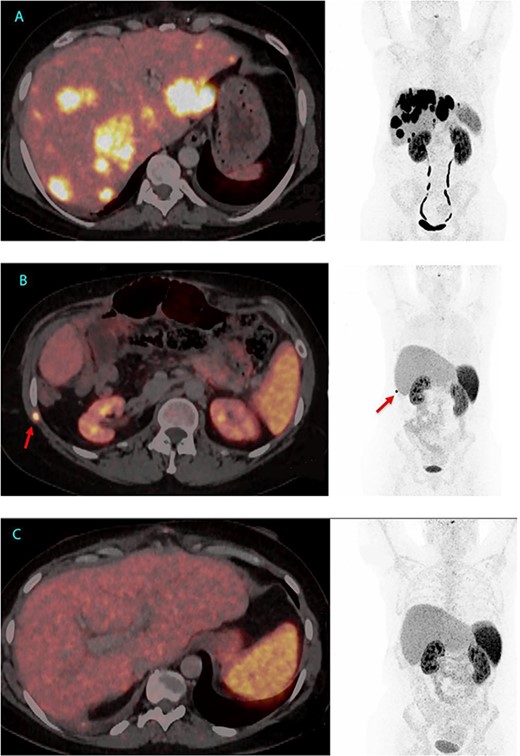

Given her declining health, the patient was placed on the LT waitlist in March 2022. After a 7-month hospital stay, she underwent an LT in June 2022. Figure 1 presents the final 64Cu-DOTATATE PET/CT prior to transplantation, demonstrating extensive hepatic involvement without extrahepatic metastases. The LT was a technical demanding and high-risk procedure because of the previous Whipple procedure, liver resections and complicated biliary leakages. Abdominal wall was closed POD 2 with a biological mesh. The transplantation was complicated by necrotizing pancreatitis, successfully treated by endoscopic, transgastric necrosectomy.

64Cu-DOTATATE PET/CT from 2 June 2022, 7 weeks before LT with extensive hepatic involvement but no extrahepatic metastases (A). 64Cu-DOTATATE PET/CT 15 months after LT revealed an implantation metastasis in the thoracic wall (B). Latest 64Cu-DOTATATE PET/CT performed 18 months after LT and 3 months after resection of the thoracic metastasis showed no signs of recurrence (C).

In the most recent 64Cu-DOTATATE PET/CT scan from January 2024, conducted 18 months after LT, there was no signs of recurrence. Currently, the patient is in good health, has started part-time work and has no hormone-related symptoms, since LT serum VIP has been below level of detection (<3.8 pmol/L) (Figs 1 and 2).